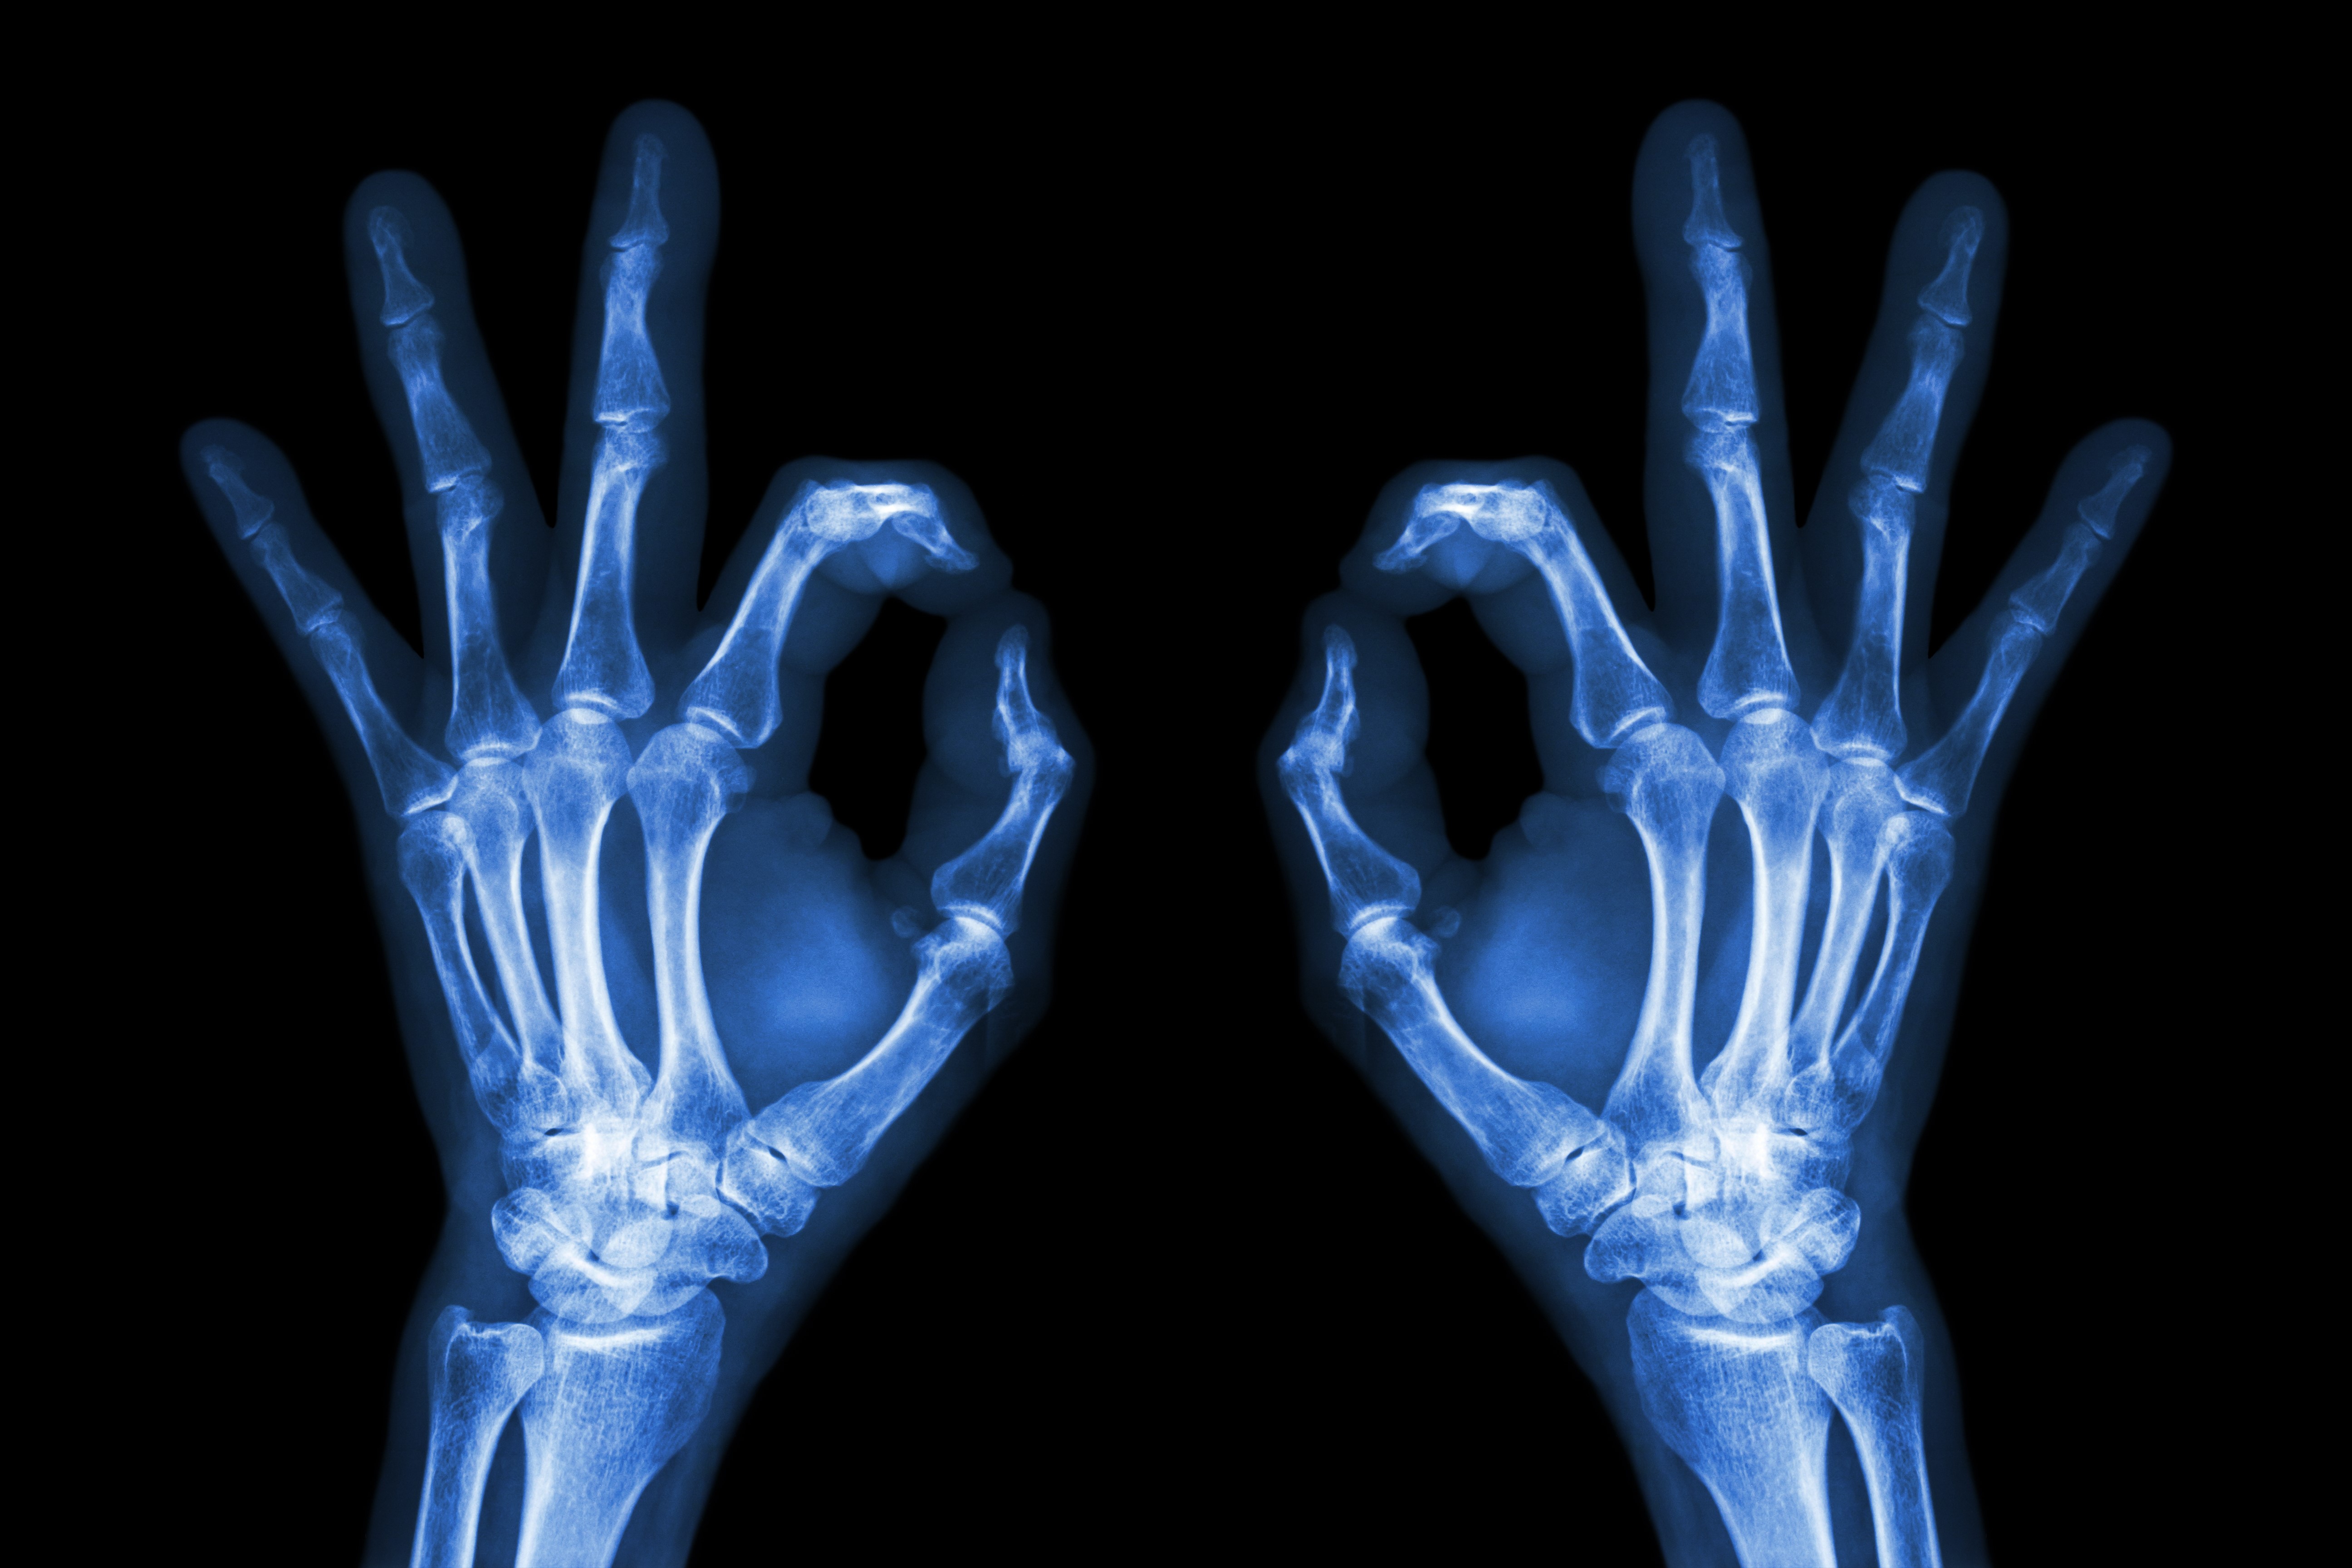

Musculoskeletale radiologie: het klinkt ingewikkeld, maar het is radiologie op het gebied van houding en beweging. Wat kun je er allemaal mee? En wat zijn de ontwikkelingen?

Radiologie is een breed specialisme wat je nog verder kunt onderverdelen. De ene radioloog houdt zich bijvoorbeeld alleen maar met het hart bezig, de ander kijkt puur naar de hersenen. Voor sommige radiologen (zoals in ons ziekenhuis) staat juist het bewegingsapparaat centraal. Denk daarbij aan botten, spieren, pezen en gewrichten. Musculoskeletale radiologie, heet dat met een sjiek woord. Naast het beoordelen van foto’s, voeren de radiologen in de Sint Maartenskliniek ook behandelingen uit. Heeft een patiënt bijvoorbeeld last van een gewrichtsontsteking, dan kan de radioloog ervoor kiezen om een geneesmiddel in dat gewricht te spuiten. Verder is het mogelijk om een biopt van bepaald weefsel of vocht af te nemen. De radioloog werkt hierin nauw samen met andere specialisten, waaronder de orthopeed en sportarts.